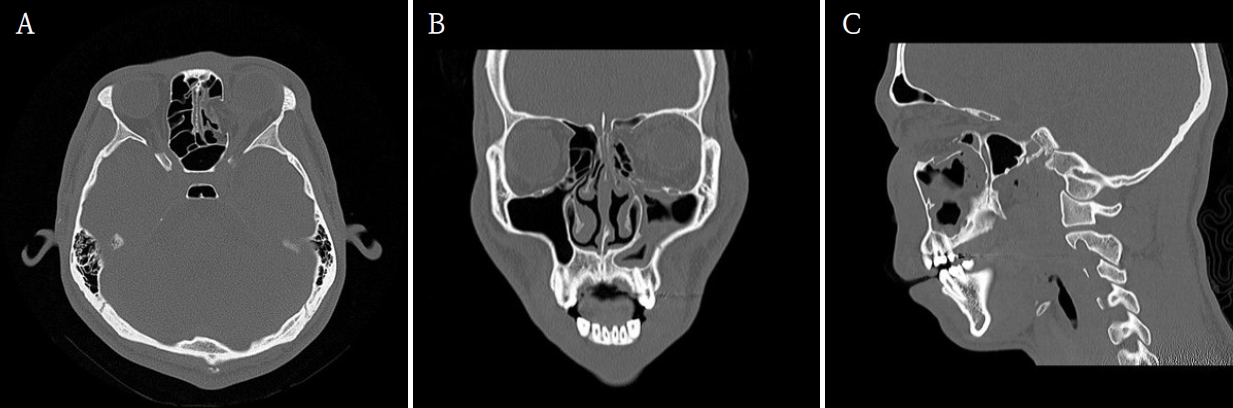

Immediate postoperative CT confirmed successful reduction of both fractures. The patient experienced complete resolution of diplopia and ocular discomfort, while infraorbital sensation remained mildly decreased but improving. At two weeks, Merocel® packing was removed, and routine dressing was performed. At two months, follow-up CT and endoscopic examination demonstrated stable reconstruction, and the silastic sheet was removed (Figs. 5 and 6). The patient’s sensation had nearly recovered, and postoperative outcomes remained stable with preserved ocular movement, normal globe position, and proper occlusion.

Postoperative computed tomographic (CT) images confirm successful reconstruction of the left medial and inferior orbital walls. A. Axial image shows restoration of the orbital contour with no residual herniation. B. Coronal image demonstrates stable support of the medial orbital wall and proper positioning of the orbital soft tissues. C. Sagittal image confirms an anatomically reconstructed orbital floor with maintained height and continuity.